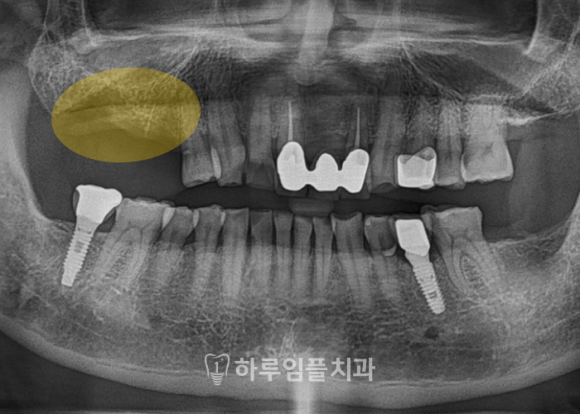

최종 보철물은

잇몸과 부드럽게 이어지며

깔끔하게 완성되었습니다.

어버트먼트 위에 정확히 안착되어,

음식물이 끼거나

잇몸에 무리가 가지 않도록 설계되어

오래 사용하시기 좋은

튼튼한 형태입니다.

이번 사례처럼

맞춤형 어버트먼트를 사용하면

음식물이 잘 끼지 않고,

잇몸 염증의 위험도 줄어들며

무엇보다도 자연치와 유사한 형태와

편안함을 얻을 수 있습니다.